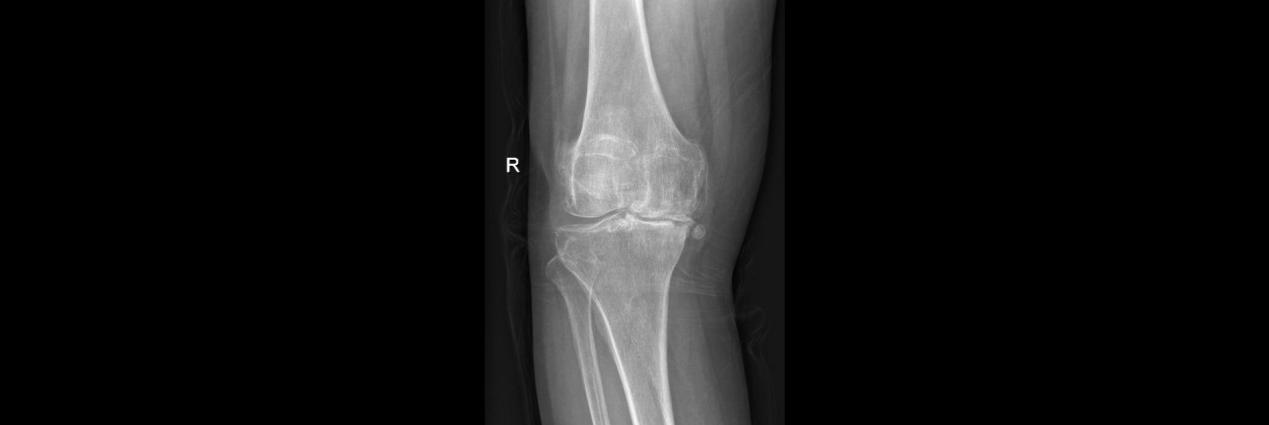

术前

66岁的孙女士,因右膝疼痛3年,加重2年于2月17日入院,患者曾接受关节腔玻璃酸钠等保守治疗,短期效果可,近期效果不明显,膝关节疼痛严重,每走一步都扎心的疼。入院后,董孟政副主任、黄贵云副主任一齐查看患者情况,经拍片检查诊断为膝关节骨性关节炎严重,定于2月19日为患者行关节置换术。